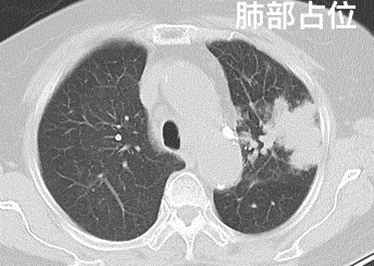

(1)占位性病变:“占位性病变”的意思,通俗地说,就是被检查的部位有一个“多出来的东西”,占据了原本应该在这里的组织的位置。这个“多出来的东西”(术语叫作“病灶”)可大可小,边界可清可粗糙,对邻近脏器或组织有一定的压迫征象。